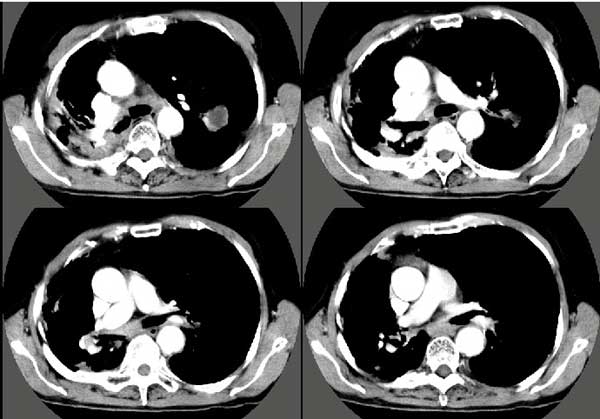

以下是引用扬仪在2005-5-12 20:46:40的发言:[br]右肺呈术后改变;双侧肺野散在分布斑片状、点状高密度病灶,(似可见“树芽征”);左上尖后段见斑团状高密度病灶(2个层面?),边缘毛糙,段性分布,与斜裂相邻,临近胸膜粘连;增强示病灶边缘强化,内呈水样密度;心影、纵隔右移,内可见4r淋巴结肿大。[br]意见:1、双肺继发性肺结核,左上为干酪病灶;[br] 2、矽肺合并感染;[br] 3、建议抗痨+抗炎。 [br]愚人之见,请高人指教!